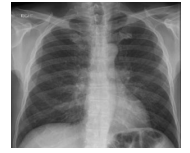

for pneumocystic pneumonia (PCP) - CXR bilateral perihilar/ground glass shadowing, bronchoalveolar lavage

CXR - perihilar infiltrates/normal